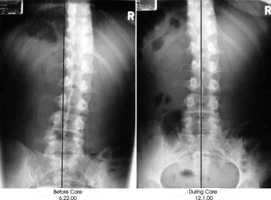

In recent years, specialized NUCCA Upper Cervical Doctors have developed a way to safely align just this "Atlas" bone, clearing the central pathway that your body uses for nerve communication and balancing the entire entire spine.

This complex, little known type of health care that involves only the correction of the"Atlas" in the neck, can restore proper function of the brain stem and nerves of your entire body. And that means healing.

This safe and gentle procedure quite simply restores body balance and proper nerve flow so that organs, limbs and tissues can resume normal functioning.

What I am saying is you could show up at their office having 20 pounds more on one foot and leave with your entire body level, square, and balanced.

If your "Atlas" is balanced, the rest of your body follows.